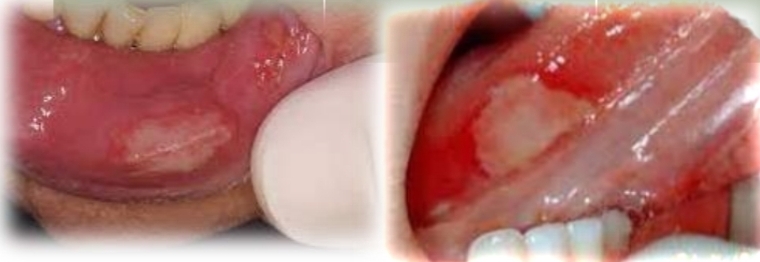

Whitish formation that comes off when rubbing, with superficial mucous tearing.

Small whitish epithelial desquamation, that leave erythematous areas between them.

Ask: Chewing habit or Anxiety? Look for adjacent poor restorations + signs of bruxism.

Morsicatio buccarum

Reactive lesion from poor fitting restoration

Mucosa chewing habit in anxiety or bruxism

Treatment - Correct habit - night splints and oral shield. (If iatrogenic correct restoration)

DD - Frictional keratosis, Leukoplakia, lichen planus, pseudomembranous candidiasis